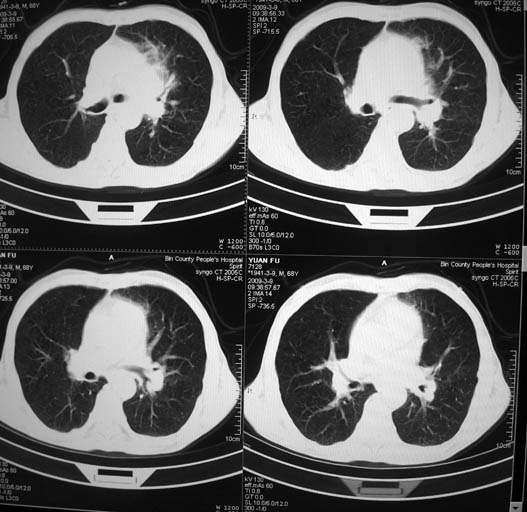

标题: CT18577:男,68岁,左肺占位。 [打印本页]

标题: CT18577:男,68岁,左肺占位。

男,68岁,左上肺占位,肺门淋巴结转移?

1)考虑左肺上叶尖段周围型肺癌并阻塞性肺炎,纵隔淋巴结转移。2)心包少量积液。

考虑左肺上叶尖段周围型肺癌并阻塞性肺炎,纵隔淋巴结转移.

1)考虑左肺上叶尖段周围型肺癌并阻塞性肺炎,纵隔淋巴结转移。2)心包少量积液

1)考虑左肺上叶尖段周围型肺癌并阻塞性肺炎,纵隔淋巴结转移。

2)心包少量积液。